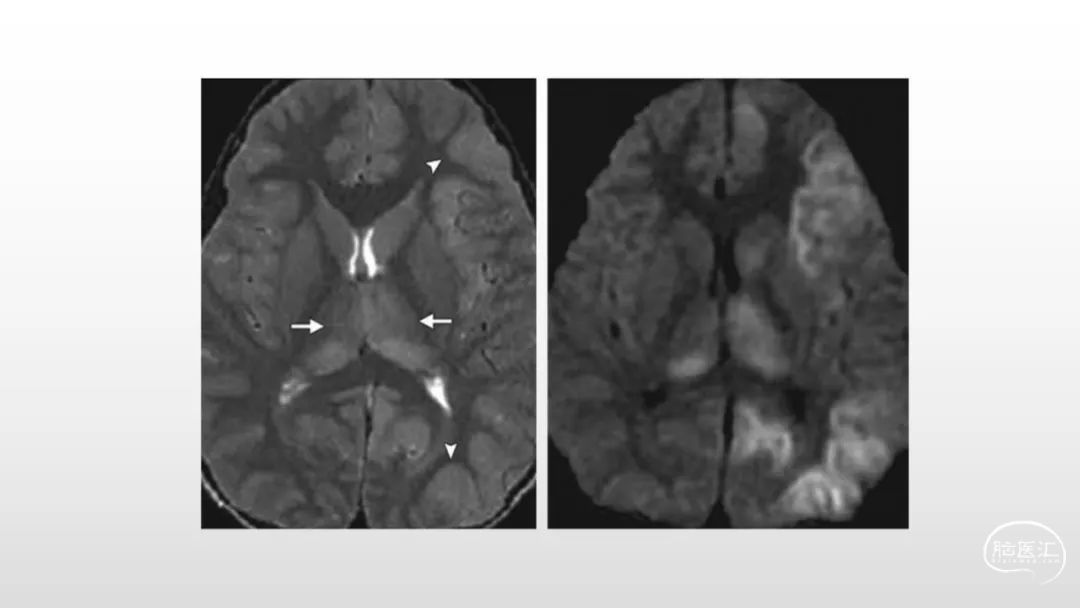

颅脑影像诊断基础知识讲座:感染和免疫性疾病1